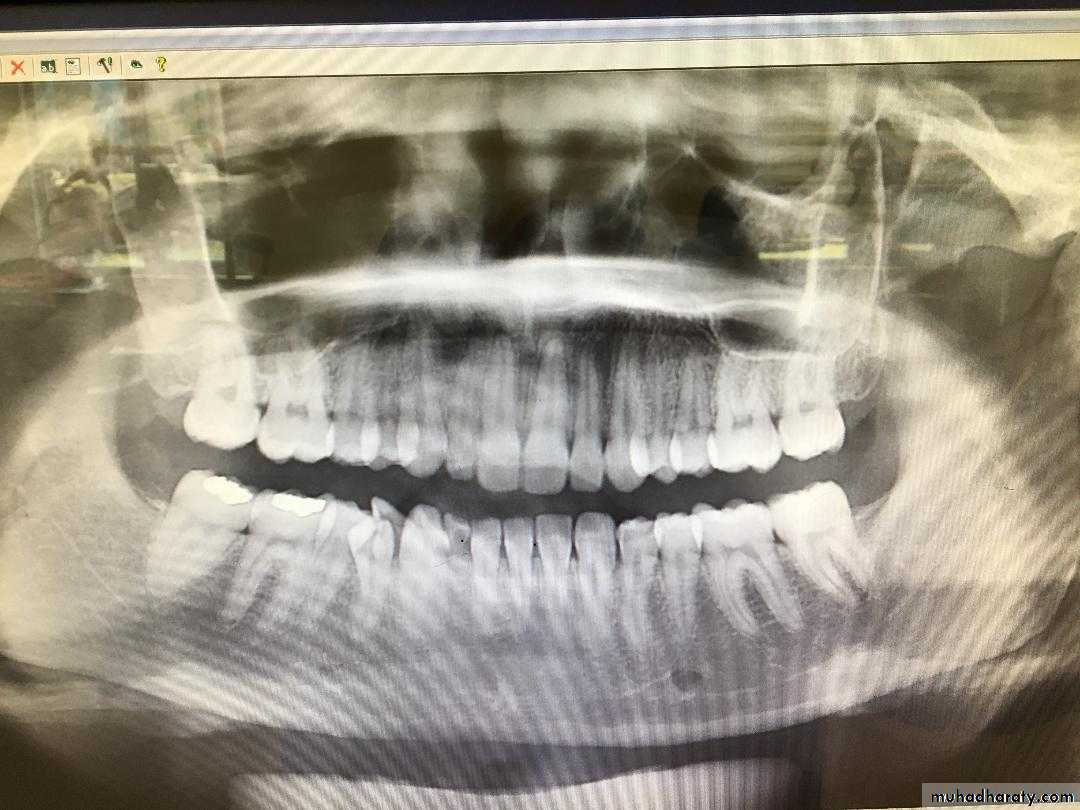

Dentin dysplasia, type I. panoramic & periapical films of the same case show the short and poorly developed roots, obliterated pulp chambers and root canals, and periapical inflammatory lesions.

Color of primary dentition is opalescent